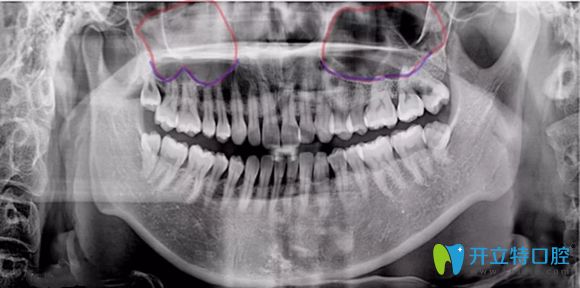

簡(jiǎn)單來(lái)說(shuō),上頜竇提升術(shù)是由于患者上頜骨高度不足,使種植體不能有效埋入,固位不行,就需要增加上頜骨高度而產(chǎn)生的手術(shù)。主要分兩種方式及內(nèi)提升和外提升。

內(nèi)提升它是指不用做額外切口,就在種植體窩洞處,用敲擊法,或者是超聲骨刀磨除上頜竇底的骨質(zhì),使上頜竇底提升。同時(shí)植入骨粉,使牙槽骨的高度也增加,這樣就能使種植體可植入的長(zhǎng)度增加,內(nèi)提升創(chuàng)傷較小,是臨床常用的方法。

外提升它適用于上頜骨高度極度不足,一般少于4mm,該情況下,可從上頜竇外側(cè)壁的骨板開(kāi)窗打開(kāi)上頜竇,剝離上頜竇底粘膜,植入骨粉來(lái)達(dá)到增加種植區(qū)域骨高度的術(shù)式。